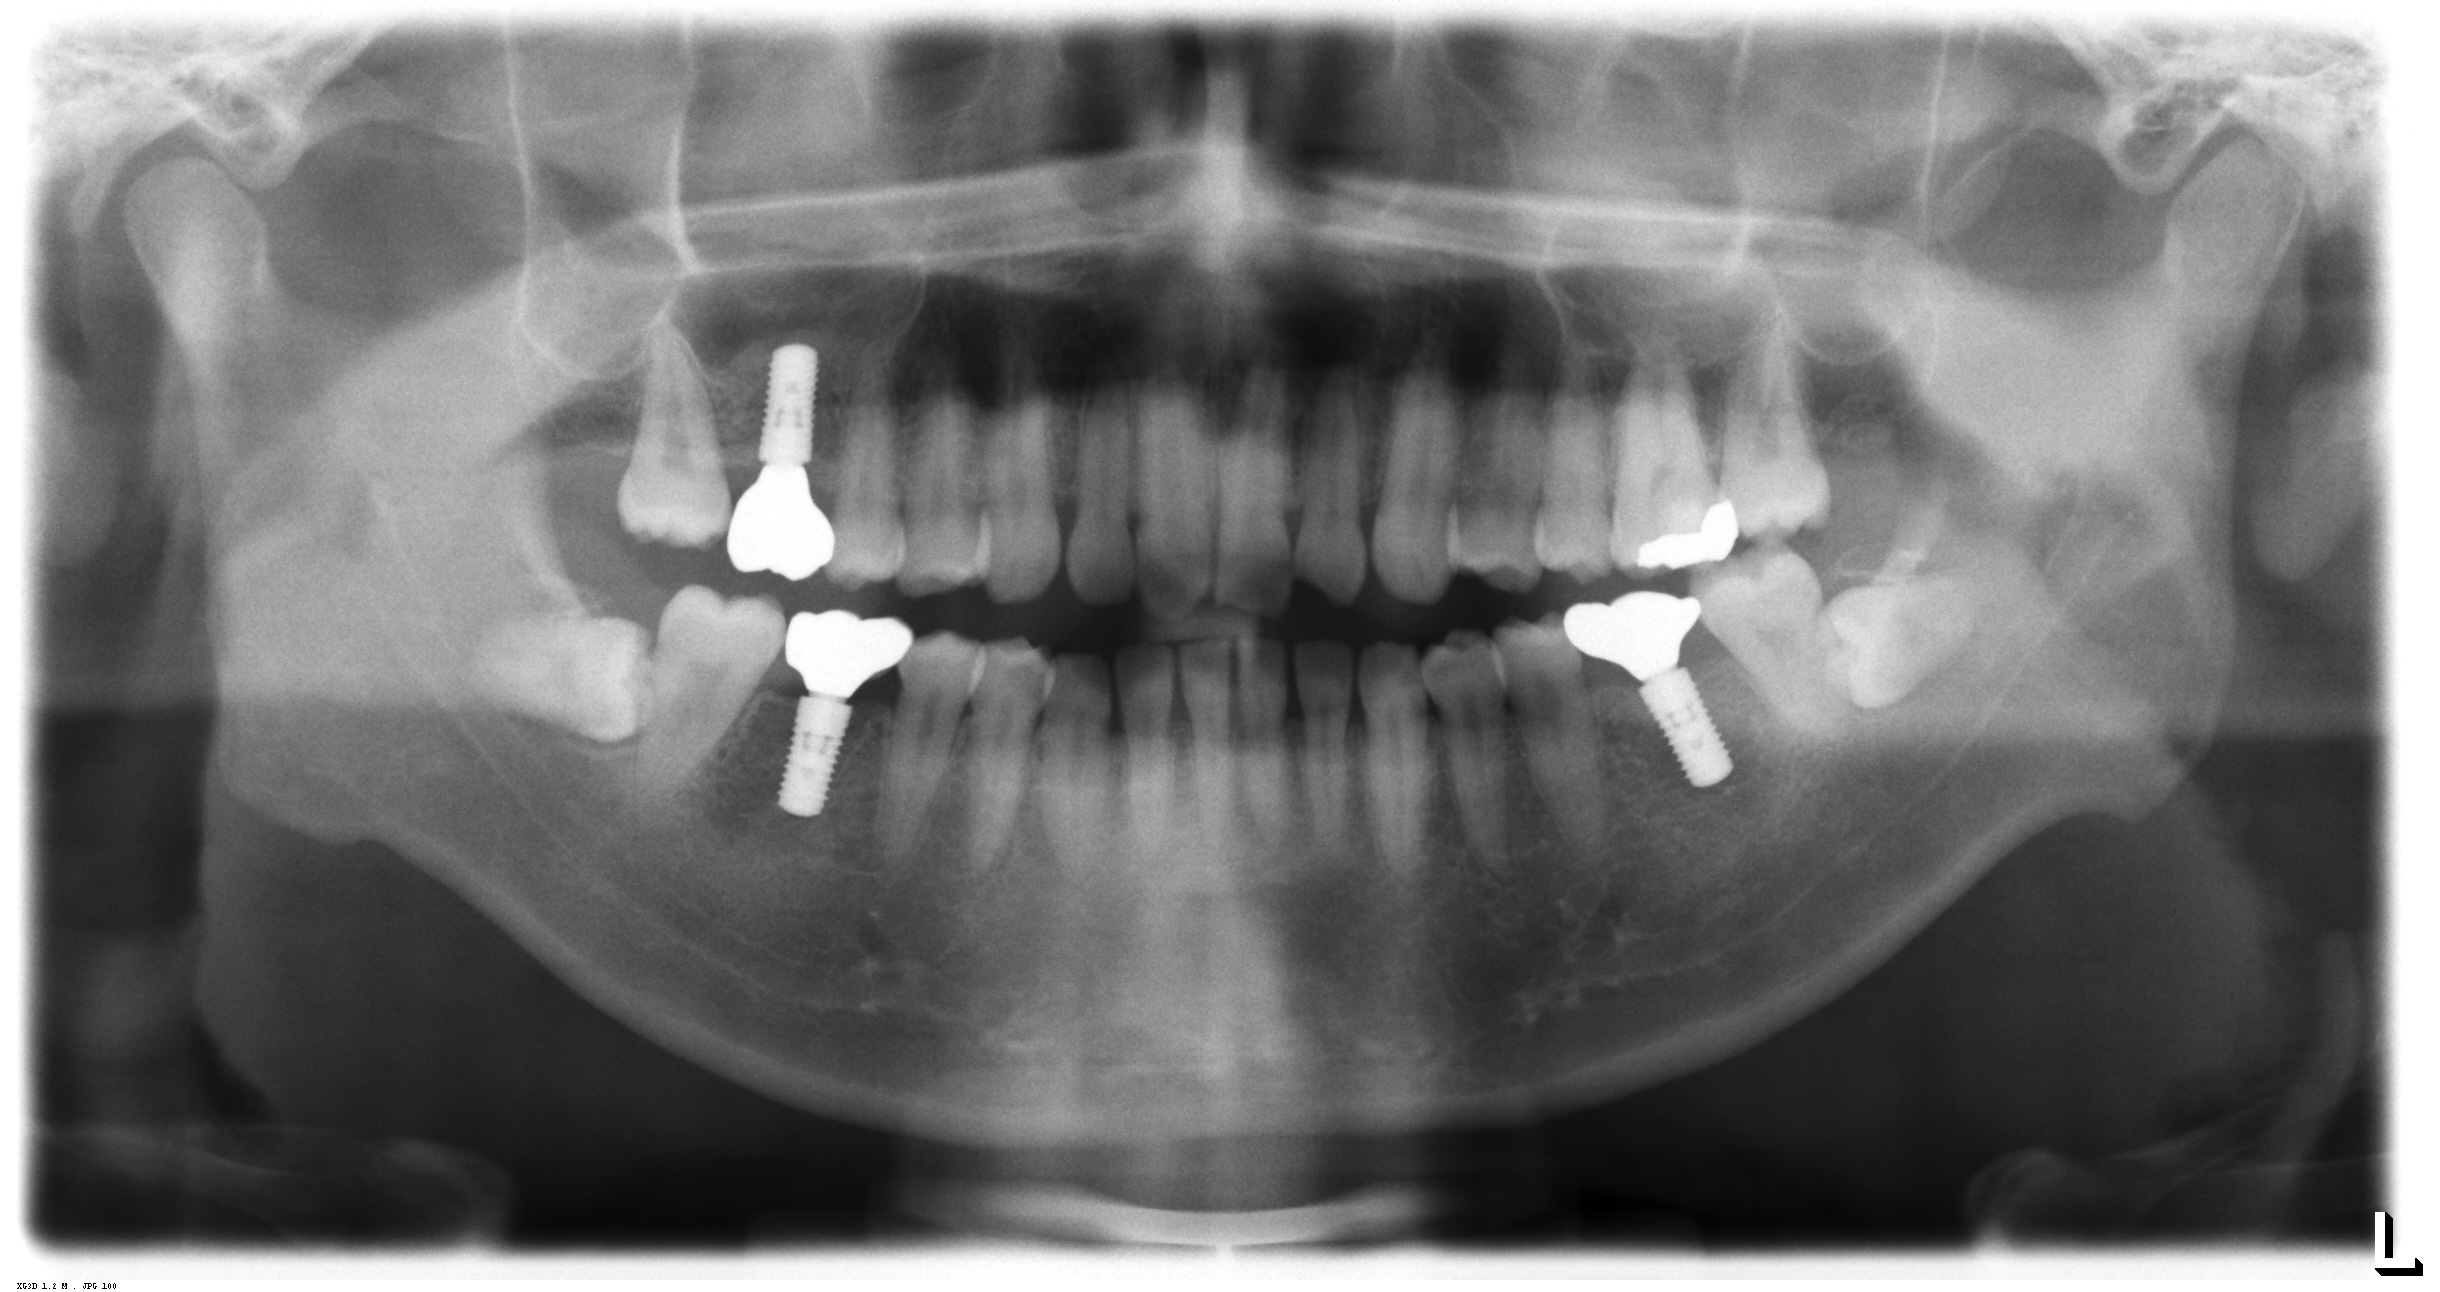

術前のレントゲン写真です。3か所の歯が抜歯となります。

上部構造が装着された後のレントゲン写真です。